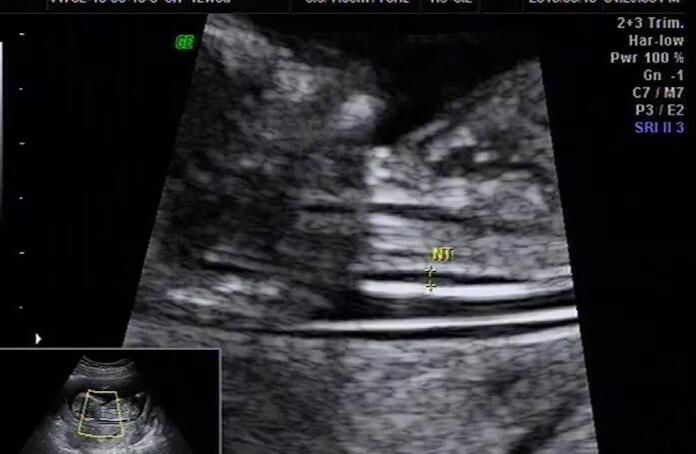

2.个性化促排卵方法及医疗费:这一部分的费用是多少与促排药物相关,通常费用5000元到20000元,试管促排期内超音波监管扫描仪也是一次100元上下;